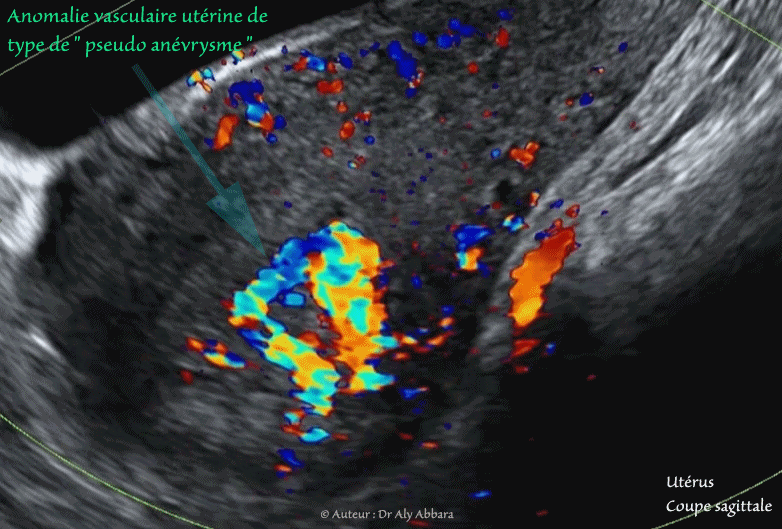

- Anomalie vasculaire utérine de type " shunt artério-veineux ou pseudo anévrysme " d'origine traumatique (accidentel)

Doppler couleur - coupes parasagittale et transverse de l'utérus

- Ce shunt vasculaire au sein du myomètre de la paroi utérine postéro-fundique est survenu chez une femme âgée de 28 ans, consultant, le service des urgences gynécologiques

pour métrorragies importantes (hémoglobine à 7,2 g/dl), survenant brutalement, trois semaine après une hystéroscopie opératoire et résection d'une rétention placentaire, suite à un avortement spontané ayant lieu 7 semaines auparavant.

- L'échographie met en évidence la présence, au sein de la paroi postéro-fundique de l'utérus, d'une lacune hypoéchogène à contour irrégulier. Le Doppler couleur montre qu'il s'agit d'une pathologie vasculaire débutant dans la cavité utérine et traversant verticalement les deux tiers de l'épaisseur myométriale profonde.

L'analyse du spectre-Doppler est en faveur de flux artériels tourbillonnants et se connectant à la circulation veineux située dans la couche superficielle du myomètre.

L'analyse du Doppler énergie volumique montre que cette anomalie vasculaire n'est pas connectée aux artères utérines.

- Le diagnostic retenu celui de shunt artério-veineux accidentel, ou un faux anévrysme.